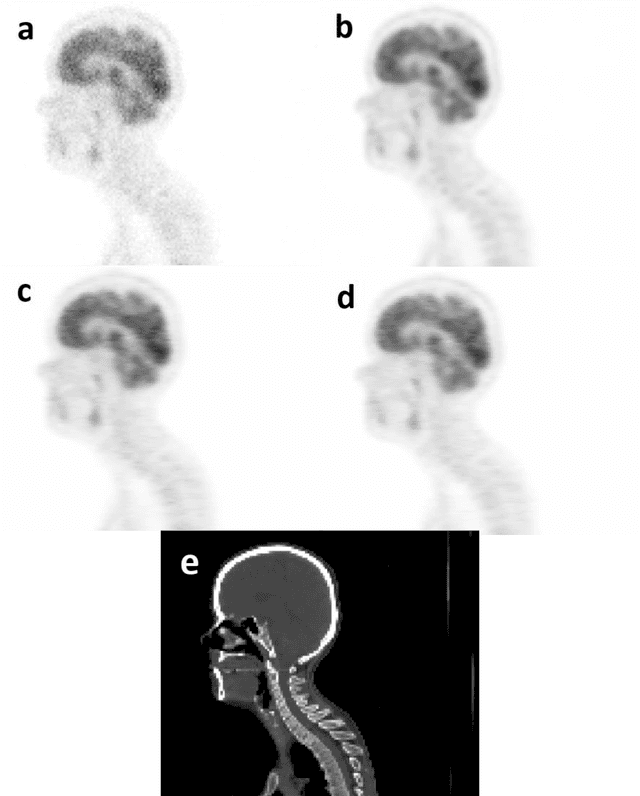

Abstract:Attenuation and scatter correction (AC) is crucial for quantitative Positron Emission Tomography (PET) imaging. Recently, direct application of AC in the image domain using deep learning approaches has been proposed for the hybrid PET/MR and dedicated PET systems that lack accompanying transmission or anatomical imaging. This study set out to investigate deep learning-based AC in the image domain using different input settings.